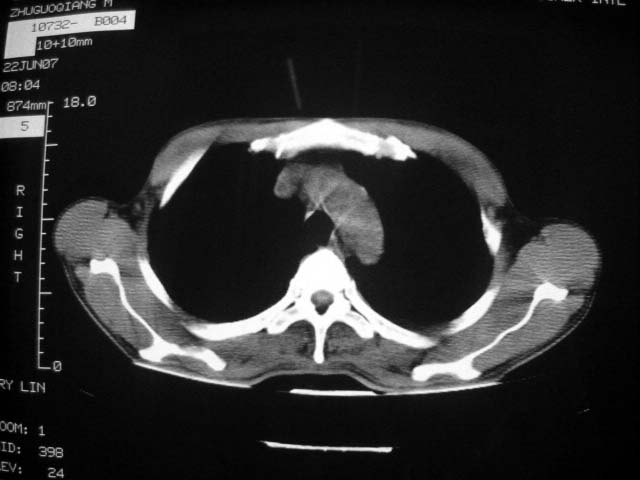

标题: CT7988D:近期图像 出乎意料!

从ct7988c 至今未用任何抗生素及抗痨药,维持保肝治疗。患者低热、咳血渐消失。

07年6月22号复查

前几次大家认为是转移癌,但此次复查病灶却明显吸收好转,不支持诊断。请大家讨论。[emb10]